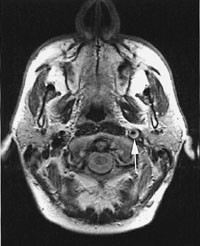

Pasient 1. Mann, 50 år. Han hadde kjent hemokromatose, men var for øvrig frisk. To dager før innleggelse fikk han gradvis økende smerter i midtre trigeminusområde på venstre side av ansiktet som strålte opp rundt venstre øye. Morgenen etter merket han at venstre øyelokk hang ned og tok kontakt med lege. Ved innleggelse var blodtrykket 170/100 mm Hg. Venstre øyelokk hang ned og tangerte pupillen, og han hadde miose og lett enophthalmus på venstre øye, forenlig med Horners syndrom. Hudsvetten var normal. Nevrologisk undersøkelse for øvrig var normal. CT av skallebasis viste ingen patologiske forhold, MR-angiografi viste en høysignalgivende veggfortykkelse og forsnevring av lumen i et kort parti over venstre a. carotis interna (fig 1). Dopplerundersøkelse viste normal blodstrøm på venstre side både i carotis communis, begynnelsen av carotis interna og carotissifongen. Man konkluderte med at det forelå en carotisdisseksjon, og han fikk acetylsalisylsyre som tromboseprofylakse.